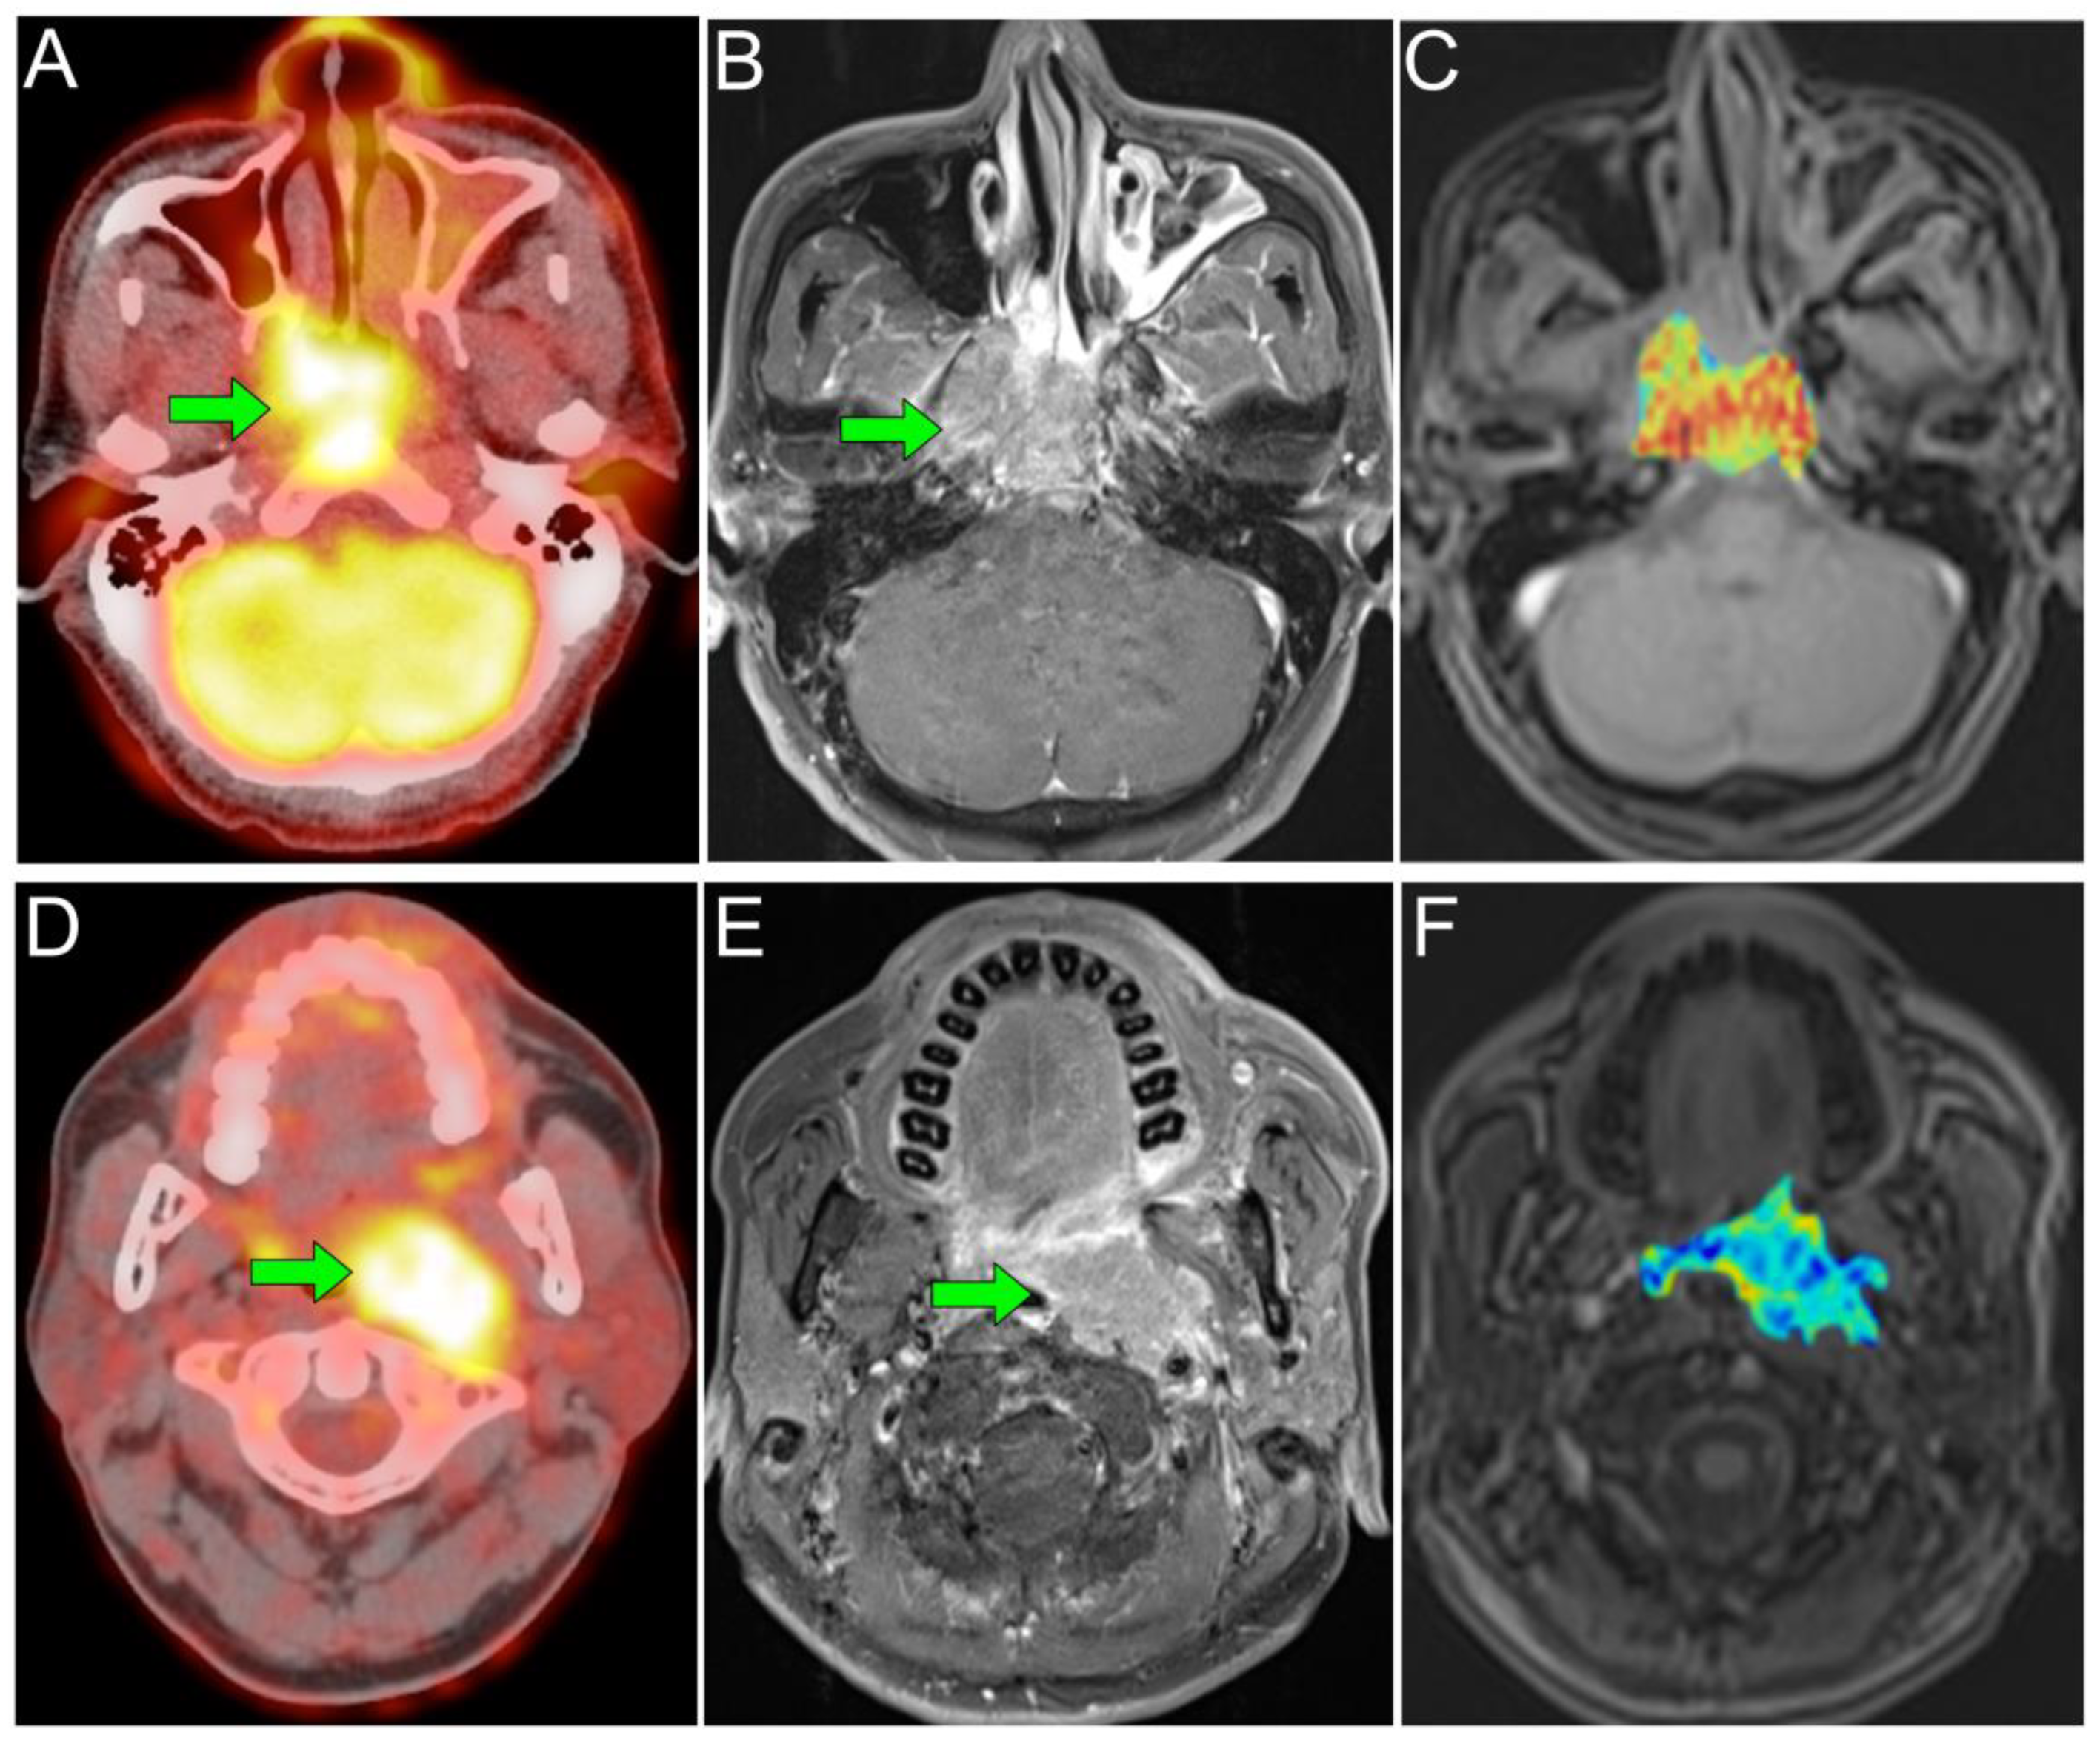

- Chan, S.C.; Ng, S.H.; Yeh, C.H.; Chang, K.P. Multiparametric PET/MRI in nasopharyngeal carcinoma: Correlations between MRI functional parameters and 18F-FDG PET imaging biomarkers and their predictive value for treatment failure. Tzu. Chi. Med. J. 2020, 33, 61–69. [Google Scholar] [CrossRef]